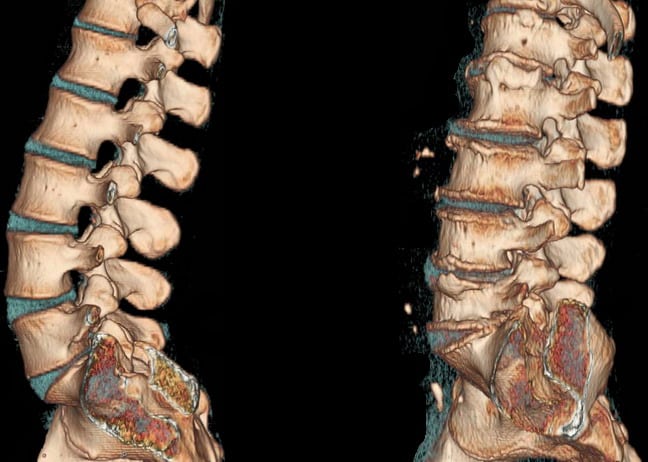

Обычный рентген не даст точное представление о развитии недуга. Чтобы определить местоположение протрузии, ее размер, тип, прочие критерии, необходимо сделать КТ или МРТ. Эти современные методы функциональной диагностики дают хорошие результаты. При компьютерной томографии используется небольшая доза рентген-излучений.